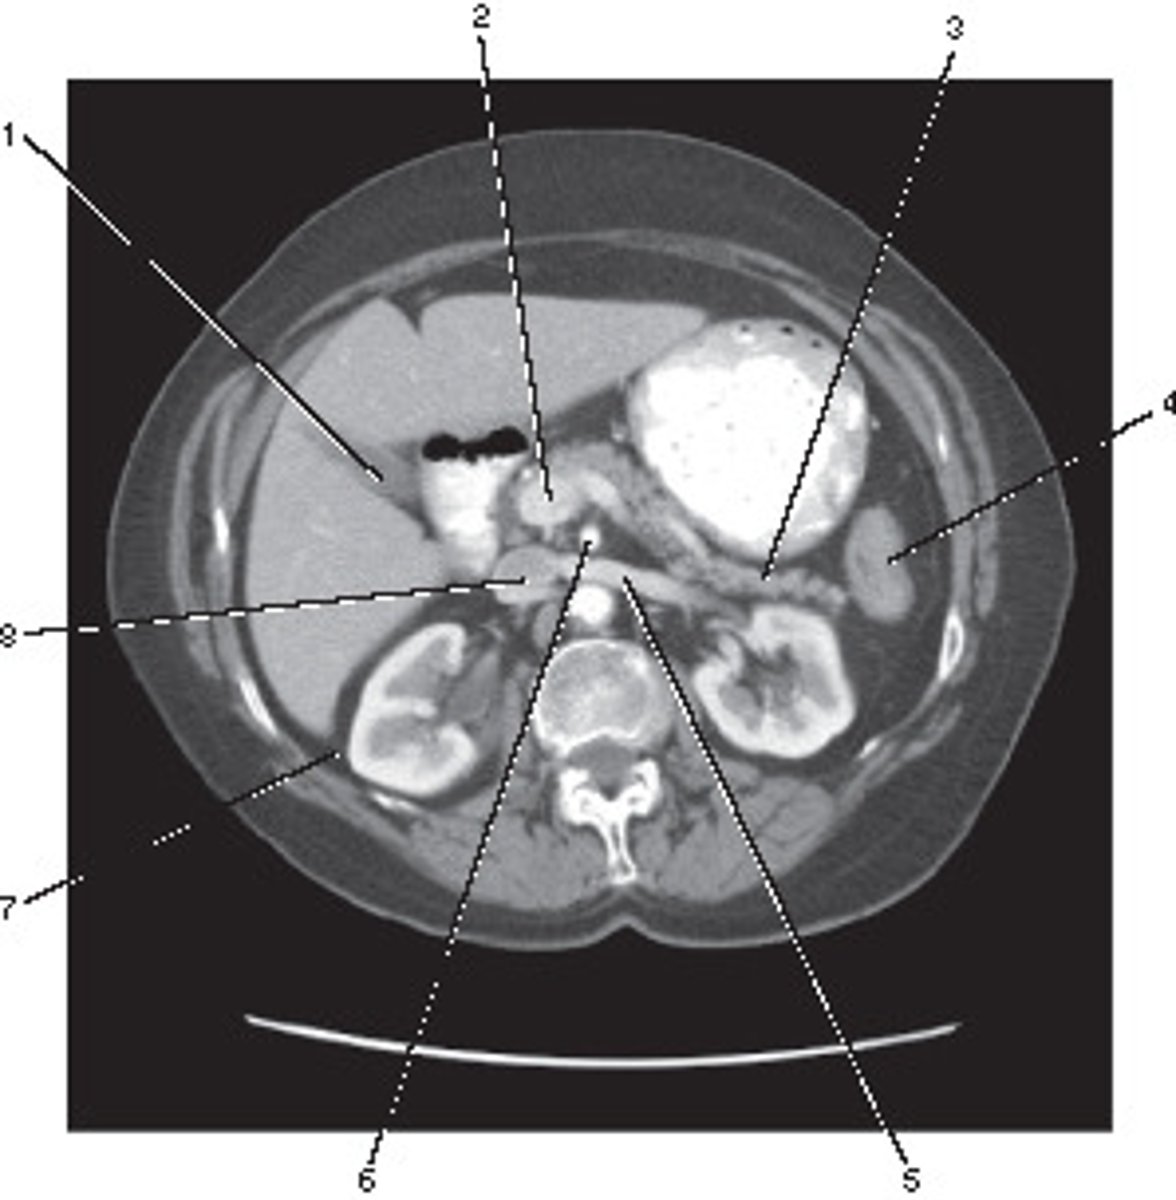

Corticomedullary;

30-40 seconds after injection,

the corticomedullary phase demonstrates optimal enhancement of the renal cortex with maximum differentiation from the renal medulla

This image of the abdomen was most likely acquired in which in which renal enhancement phase?

<p>This image of the abdomen was most likely acquired in which in which renal enhancement phase?</p>

Renal Cortex

Number 1 corresponds to which of the following?

<p>Number 1 corresponds to which of the following?</p>